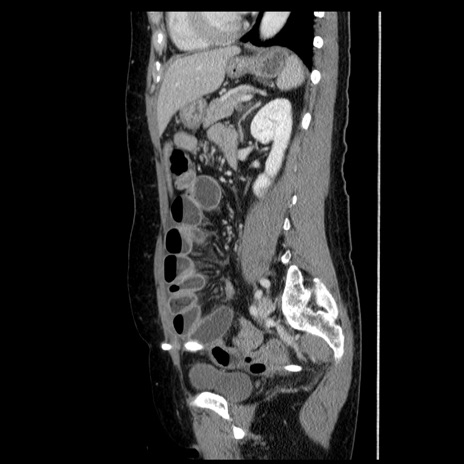

冠状断像